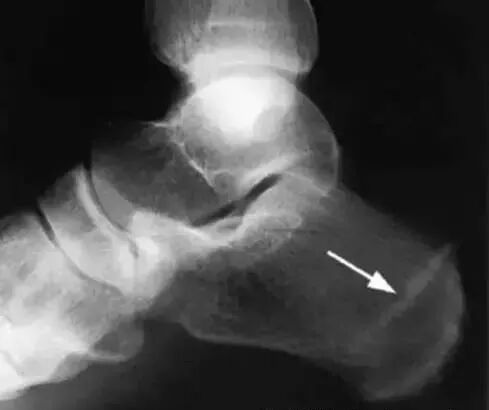

侧位X射线片显示跟骨骨刺。但是有骨刺不一定有足跟痛,跖筋膜炎不一定有骨刺。

全身最大的跗骨,跟骨的压缩骨折(图 5)并不常见,其发生率仅位于跖骨之后。好发于运动员,军人,以及骨质疏松的老年人。多由于反复的负荷过重以及骨吸收与成骨不一致引起。

图 5 跟骨压缩骨折:跟骨侧位片箭头所示

跟骨侧位片在症状产生 2-8 周后可以显示跟骨骨小梁的破坏,尽管这些图片在疾病的早期多被认为正常。与正常骨小梁垂直的硬化骨线预示着压缩骨折的愈合。当疼痛持续而平片没有证据时,MRI 或者骨扫描有助地诊断。